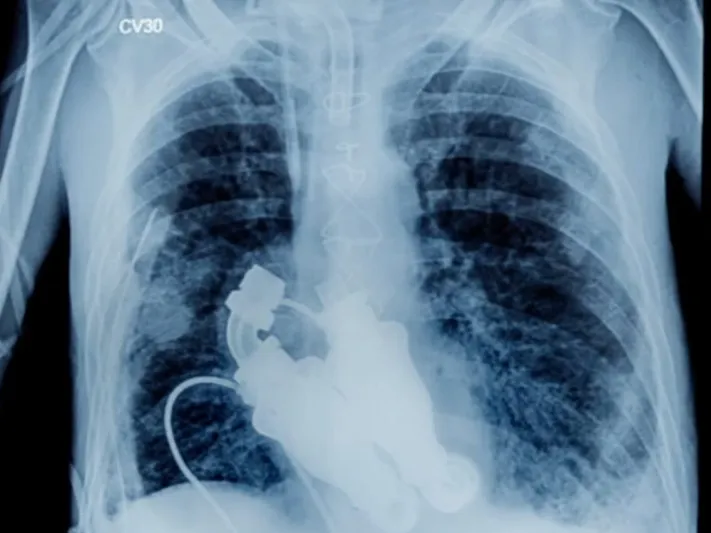

وقام الطبيبان بيلي كوهن وبود فرايزر بتثبيت جهاز "التدفق المستمر" والذي يسمح للدم بالدوران داخل جسم الإنسان دون الحاجة لنبض القلب، مما ساعد على إنقاذ حياة "كريج لويس" صاحب 55 عامًا بعد أن أوشك على الاحتضار بسبب إصابته بمرض "داء النشواني"، وهو مرض مناعي نادر يؤدي إلى امتلاء الأجهزة الداخلية ببروتين لزج يسبب تسارعاً في دقات القلب وفشلاً في الكلى والكبد.

ويعمل جهاز "التدفق المستمر" أو (LVAD)، على محاكاة وظائف البطينين الأيمن والأيسر للقلب والقيام بالوظائف الحيوية للقلب بشكل طبيعي دون وجود نبض أو ضربات قلب.